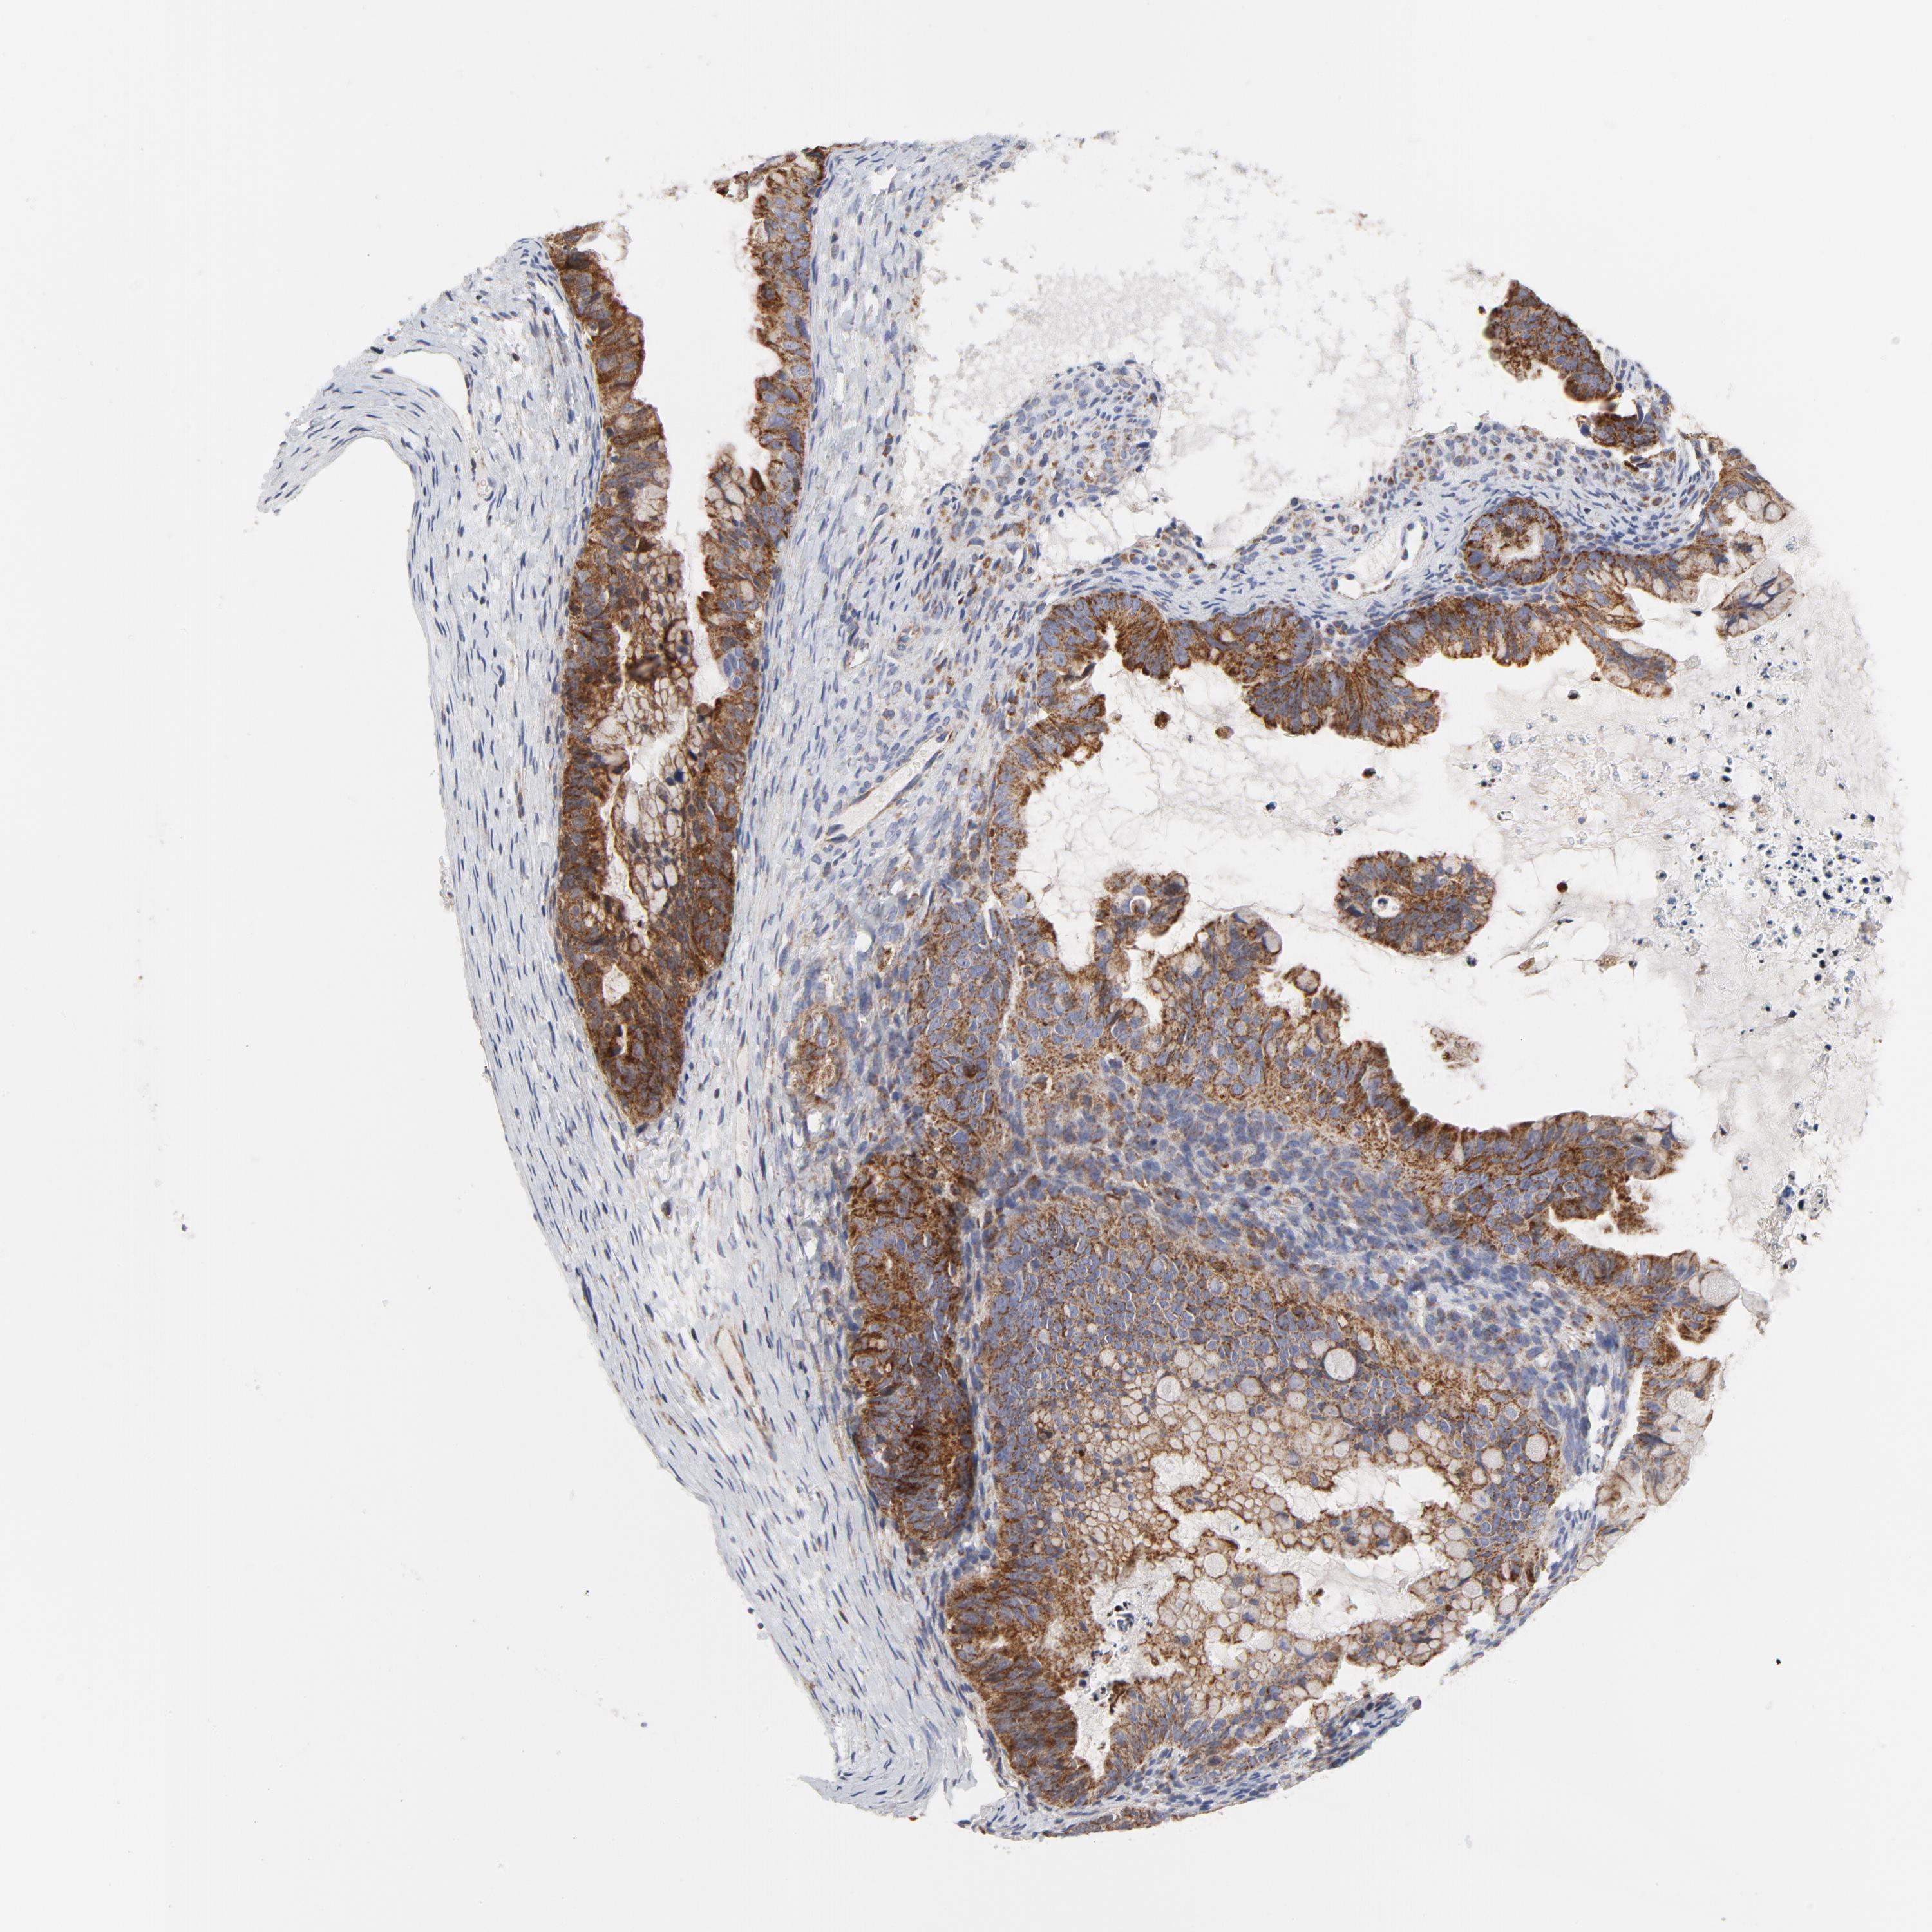

OVARIAN CANCER - Protein expressioni

A mouse-over function shows sample information and annotation data. Click on an image to view it in a full screen mode. Samples can be filtered based on level of antibody staining by selecting one or several of the following categories: high, medium, low and not detected. The assay and annotation is described here.

Note that samples used for immunohistochemistry by the Human Protein Atlas do not correspond to samples in the TCGA dataset.

Antibody stainingi

Antibody staining in the annotated cell types in the current human tissue is reported as not detected, low, medium, or high, based on conventional immunohistochemistry profiling in selected tissues. This score is based on the combination of the staining intensity and fraction of stained cells.

Each image is clickable and will lead to virtual microscopy that enables deeper exploration of all samples and also displays staining intensity scores, fraction scores and subcellular localization as well as patient and tissue information for each sample.

Antibody CAB004222

Cystadenocarcinoma, serous, NOS

Cystadenocarcinoma, mucinous, NOS

Carcinoma, endometroid

Carcinoma, NOS